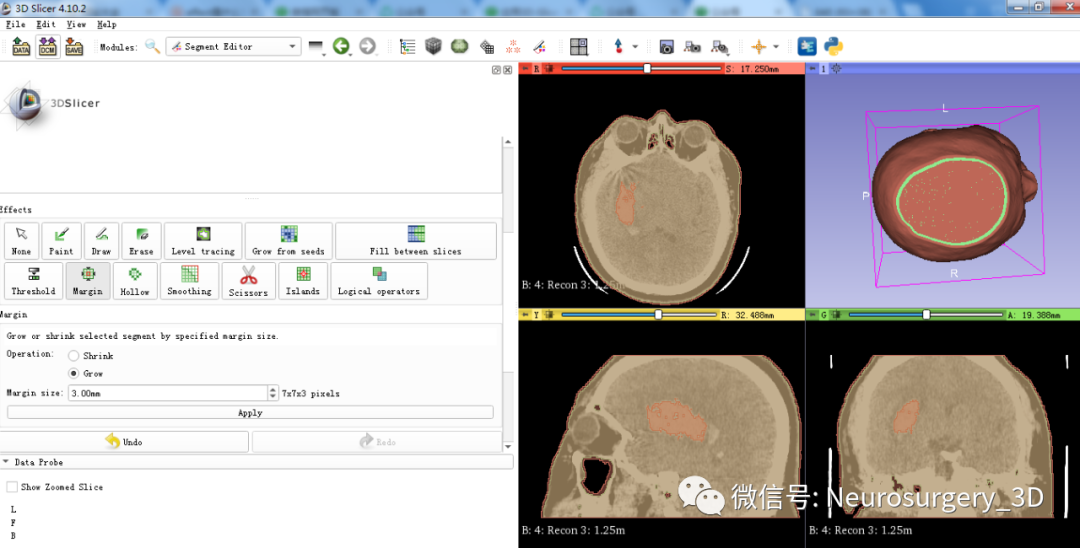

一)利用segment editor![]() Margin

Margin![]() 中的Grow和逻辑运算模块生成面具模型

中的Grow和逻辑运算模块生成面具模型

2、利用Margin![]() 中的Grow膨胀Mo xing_2,可见图中红褐色大于绿色模型。

中的Grow膨胀Mo xing_2,可见图中红褐色大于绿色模型。